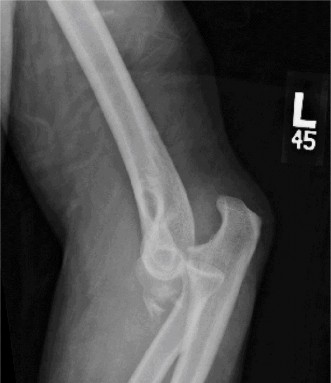

CT arthrograms of the patient’s left shoulder are shown in Figure 2–56. CRP is <3, ESR 45. The patient continues to have pain, so you decide to perform arthroscopic biopsy to obtain tissue cultures. Frozen sections show <5 PMNs per hpf, and Gram stains are all negative.

Figure 2–56

The correct answer is (B). Figure shows contrast under the glenoid component. Given the patient’s normal inflammatory markers and frozen sections combined with continued pain and loosening on CT, infection with P. acnes(an organism that is very difficult to isolate) should be investigated by holding any cultures for at least 2 weeks to see if it will eventually grow. Chocolate agar (Choice C) is mainly used for growing species such as H. influenzae and Neisseria meningitidis not P. acnes. A is incorrect since the patient’s cell count and frozen sections are clearly abnormal, therefore referral to pain clinic would not be appropriate. However, Choice D would be too aggressive an approach given that no organisms have been isolated, frozen sections show <5 PMNs per hpf, and the patient has relatively normal inflammatory markers.